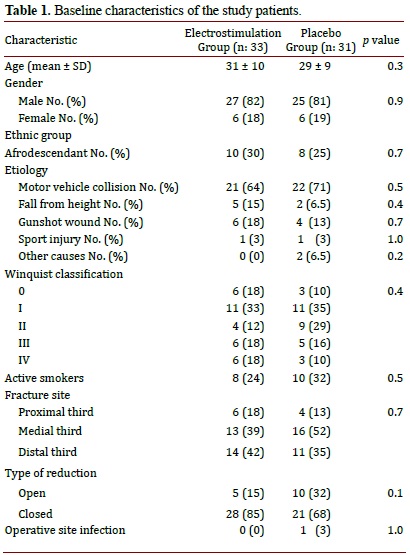

Baseline characteristics such as age, gender, race, etiology, fracture severity, and fracture site were similar between groups. The mean age among patients was 30.2 years, the ratio between men and women was 4:1, and most suffered a motor vehicle accident. Active smokers and those who quit smoking in the past six months were grouped together as smokers. For smoking and type of reduction (open vs. closed) no statistically significant difference was noted. All of this is shown in Table 1.